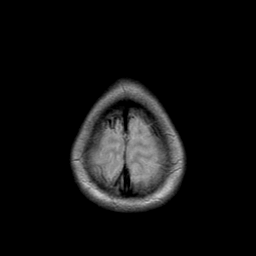

Metastatic bronchogenic carcinoma: proton density-weighted MR -- Slice #21

[Home][Help][Clinical] Slice 21